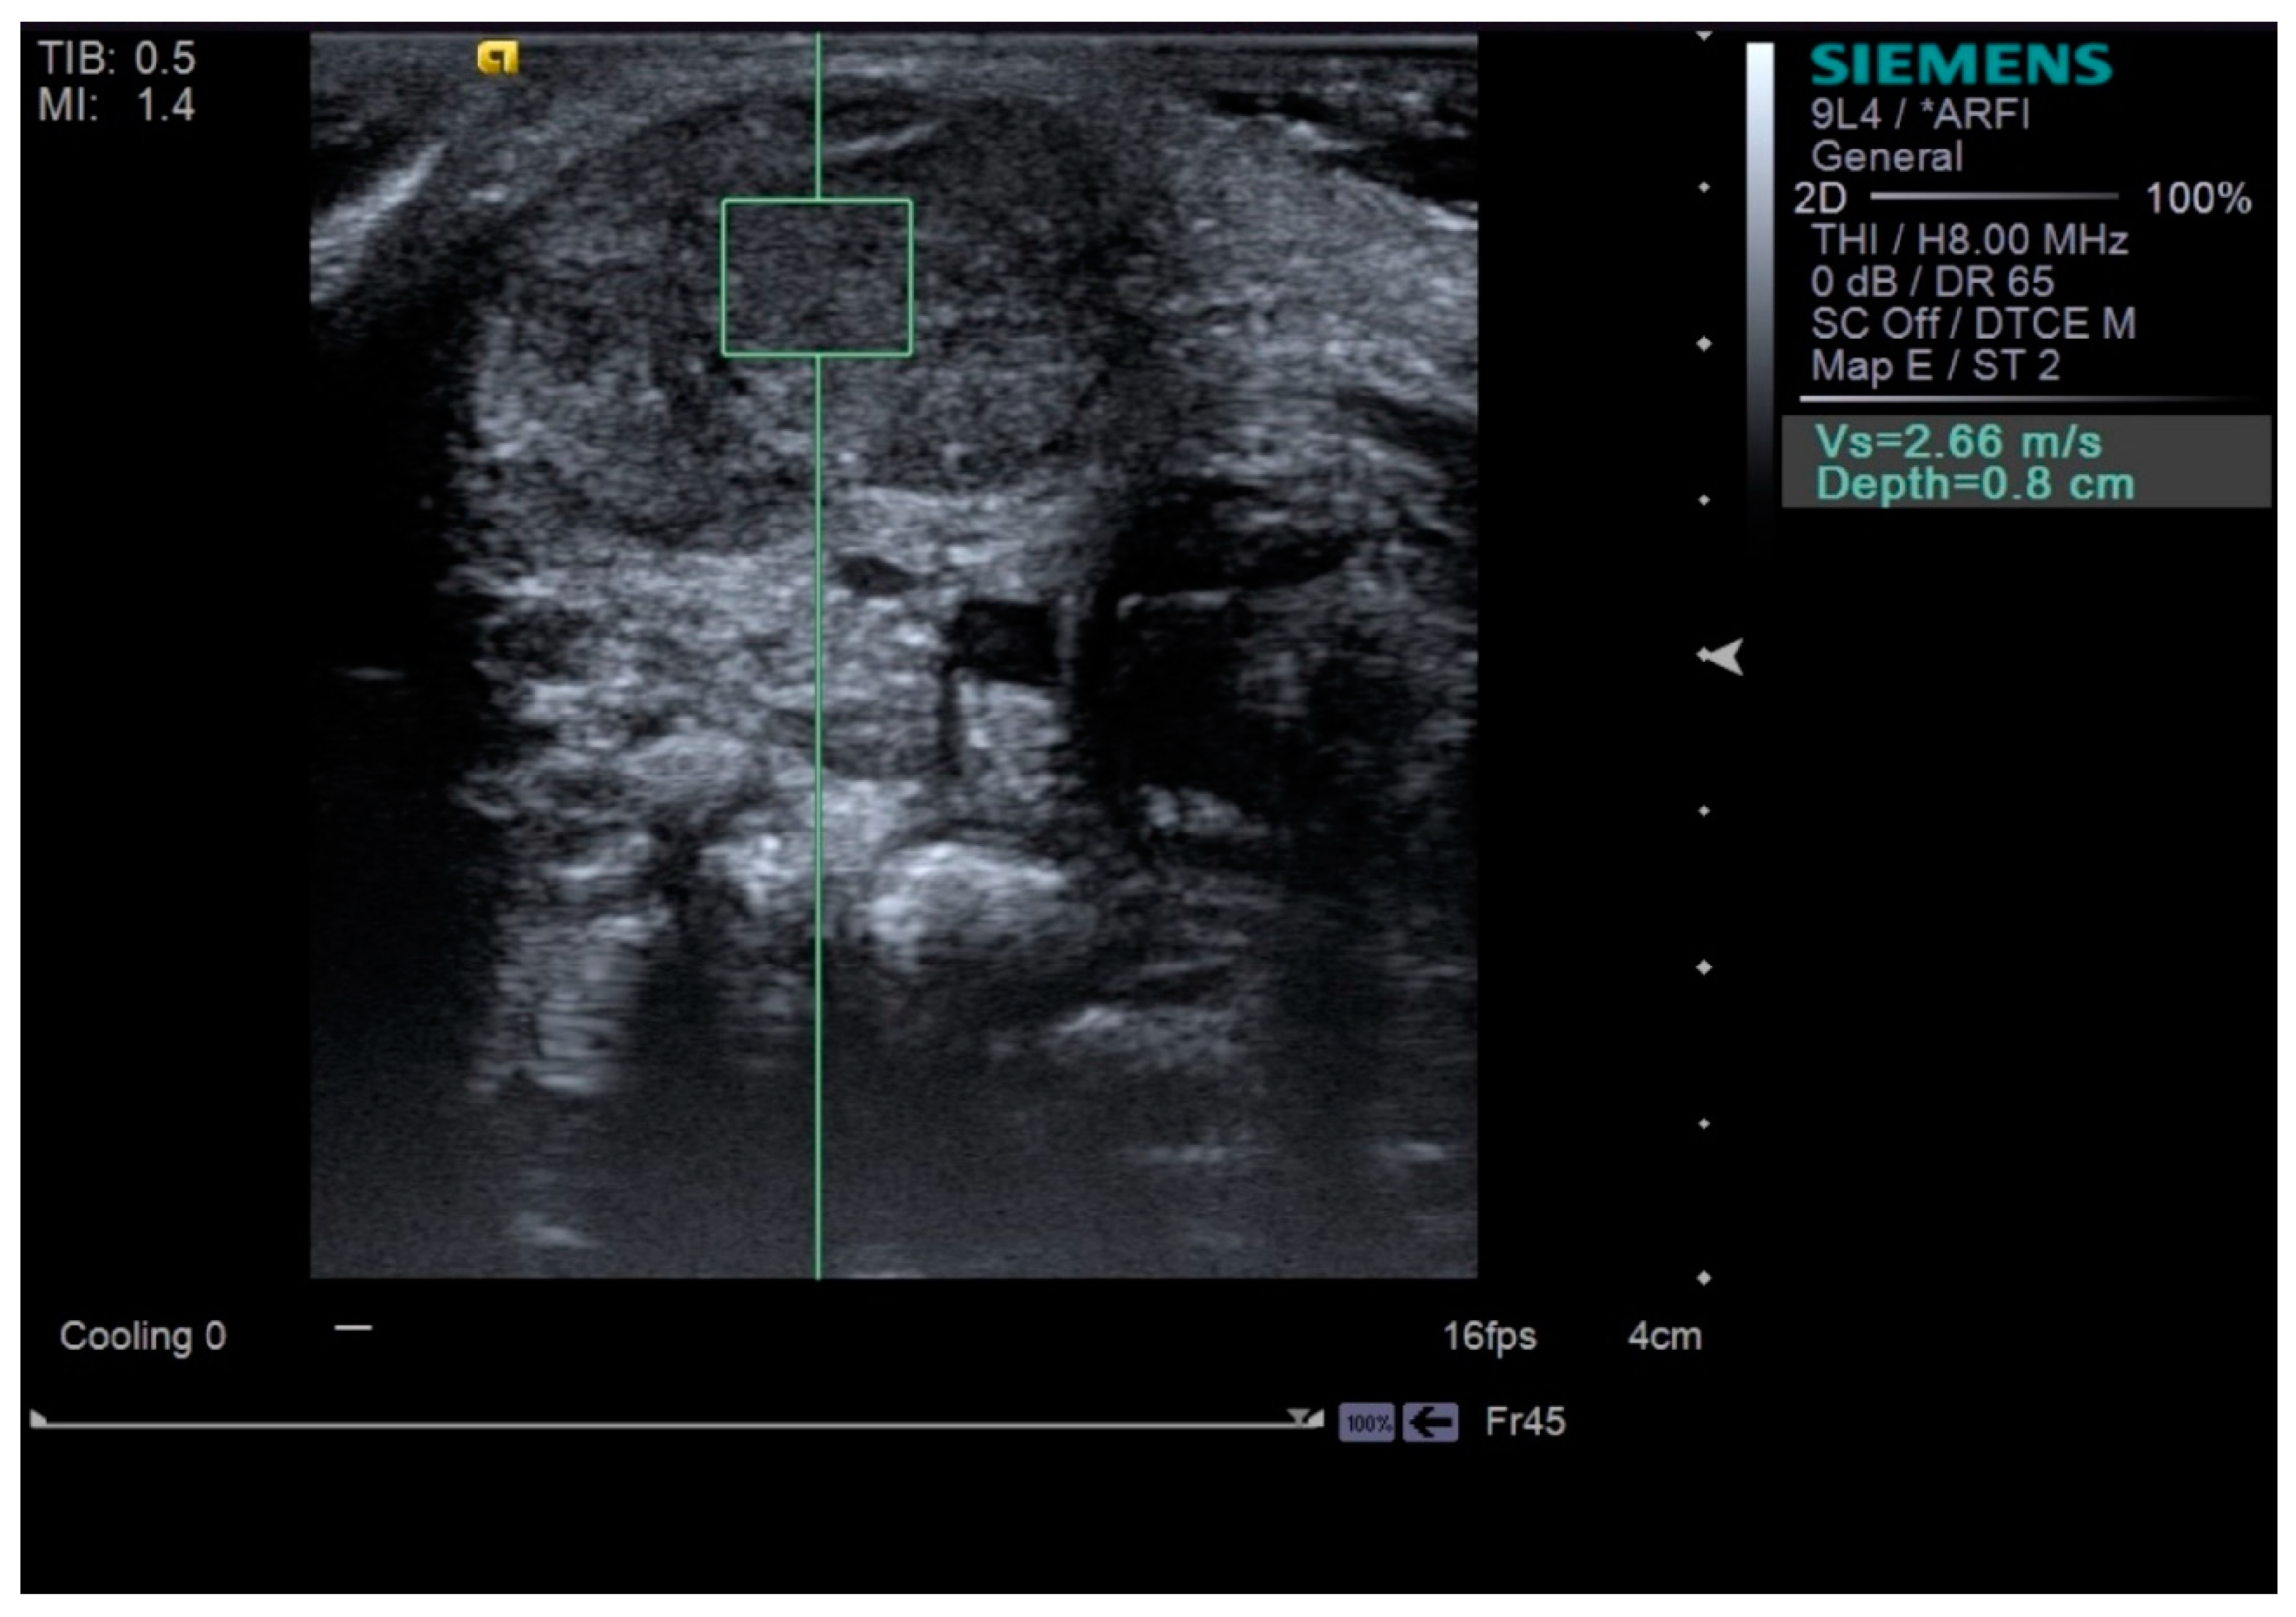

Neck ultrasonography was performed while the infants were asleep in a supine position, with slight rotation of the head to the opposite side. A small pillow was used to support the neck, and the infant’s position was also supported by the parents (Figure 1). Scanning was paused temporarily if the infant was uncooperative and cried. The ultrasound procedure was carried out by a skilled physiatrist with > 4 years of experience, using a Virtual Touch Imaging, ACUSON S2000 Ultrasound Unit (Siemens, Mountain View, CA, USA). The thickness of the affected SCM mass was measured in the longitudinal and transverse planes in ultrasound B mode with a linear probe of 5–14 MHz frequency bandwidth (Figure 2). The distance from the superficial to the deep fascia at the thickest portion of the SCM was measured using electronic calipers. The thickness of the unaffected SCM was also measured at the same level as the affected SCM. The SWV of the bilateral SCM was measured using ARFI in the transverse plane (Figure 3). The region of interest was selected to cover the entire SCM. Stronger manual compression increased the speed of shear-wave propagation, and the examiner therefore aimed to apply minimal compression during measurement of the SWV. SWV was measured three times at bilateral SCM muscles, and the median value was used for analysis. The ROM of neck rotation and lateral flexion were measured bilaterally using an arthrodial goniometer (Figure 4).

Figure 3.

Shear-wave velocity measured by scanning in the transverse plane at the bulbous portion of the sternocleidomastoid muscle (green square means the region of interest).